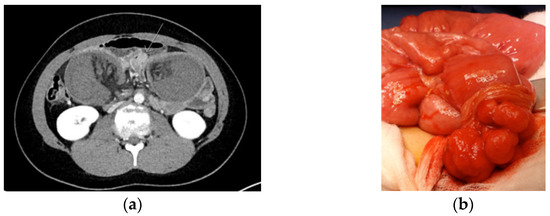

| PJS patients with an episode of acute severe abdominal pain and/or suspicion of intussusception should urgently be referred to a surgical unit, preferably a dedicated center. If, after clinical and diagnostic evaluation the event of small bowel intussusception is not ruled out, emergency surgery (even in diagnostic intent) is recommended. Level of evidence: moderate/low Strength of recommendation: strong |

| At surgery, the preferred strategy of treating an intussusception is to dessuscept, if safe to do so. If successful, the polyp that acts as a hypomochlion should be removed by enterotomy with resection of the (pedunculated) polyp at the base. In addition, the entire small bowel should be critically inspected for further relevant polyps, and all polyps > 15 mm should be removed by enterotomy or by intraoperative enteroscopy. Depending on the distance between the polyps, an enterotomy in between polyps allowing for removal of multiple polyps via one enterotomy is preferred. Level of evidence: moderate/low Strength of recommendation: strong |